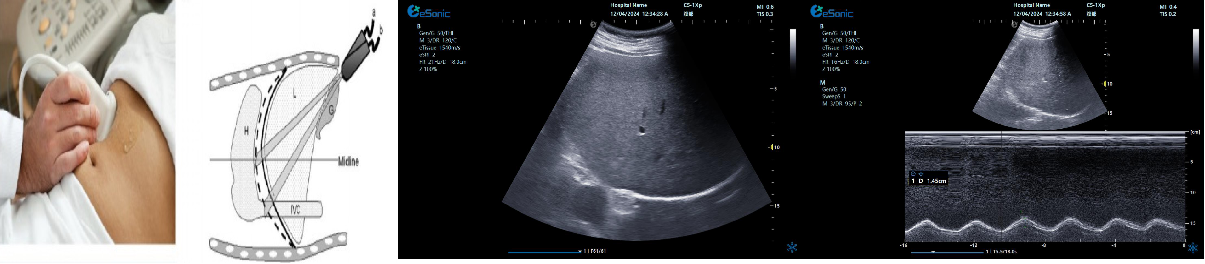

剑突下下腔静脉切面

扫查方法:在剑突下四腔心切面的基础上逆时针调整探头,直至标记指向被检者的头部,轻轻将探头向被检者右边倾斜。

超声声像图:显示右房,下腔静脉及肝静脉,注意观察下腔静脉及肝静脉有无扩张及搏动。

膈肌厚度检查

image.png

探头:高频线阵探头

部位:放置于腋前线与腋中线,7/8肋间或8/9肋间,沿肋间隙放置,观察和测量膈肌的厚度。

功能:M型超声,膈肌测量包

膈肌厚度变化

膈肌厚度测量

呼气末膈肌厚度正常值为2.0-3.5cm

膈肌活动度检查

探头:低频探头

部位:放置在腋前线或锁骨中线与肋缘交界处,启用M模式取样线垂直于膈肌,观察和测量膈肌运动幅度。

功能:M超,膈肌测量包

膈肌活动度测量